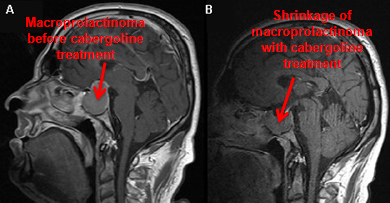

Post-menopausal women with microadenoma or undetectable pituitary mass do not usually require any treatment. Galactorrhoea usually improves when endogenous oestrogen decreases post-menopausally.[Figure caption and citation for the preceding image starts]: Gadolinium-enhanced magnetic resonance imaging (coronal view) showing a 40 mm pituitary macroprolactinoma in a 41-year-old man before (A) and after (B) 2-month treatment with cabergolineFrom the collection of Dr Ilan Shimon [Citation ends].

[Figure caption and citation for the preceding image starts]: Gadolinium-enhanced magnetic resonance imaging (sagittal view) showing a 40 mm pituitary macroprolactinoma in a 41-year-old man before (A) and after (B) 2-month treatment with cabergolineFrom the collection of Dr Ilan Shimon [Citation ends].